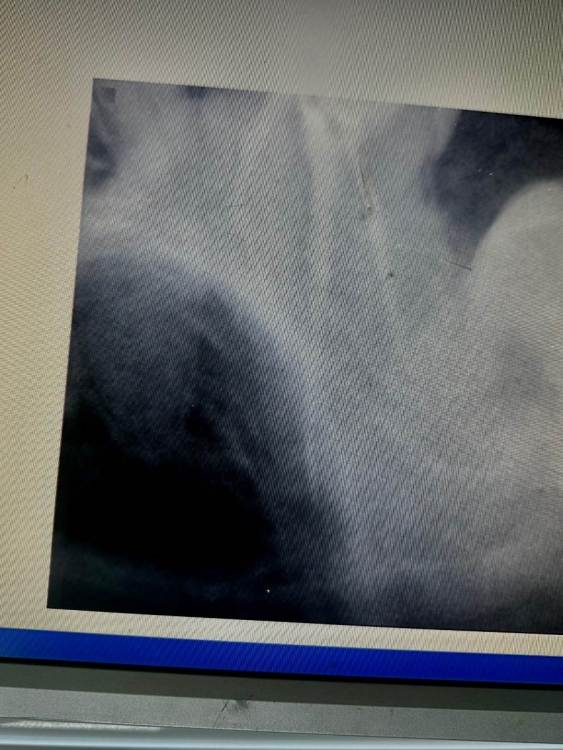

Здравствуйте!16 дней назад пролечили 7 верхний зуб. Сразу после началась сильная боль, которая держалась 2 дня и потом пошла на спад. На 7 день она остановилась и держится на одном месте. Зуб реагирует когда постучишь по временной пломбе. Когда поешь, потом начинал ныть. Так же легкие, редкие распирающие и пульсирующие боли. На зуб Накусывать неприятно. Несколько раз ломило от него все зубы, а до него было больно даже языком дотронуться.  В легком дискомфорте все это сохранялось 7 дней. На 13 день доктор распломбировала каналы, зуб поболел после распломбировки день, после вмешательства, как все утихло  и опять  я чувствую тот же дискомфорт, т е после распломбировки каналов ничего не изменилось, все держится на одном месте. сейчас в каналах кальций.Возможно ли что каналы зря распломьировали?  И проблема не в них. При удалении нерва доктор сказал, что кровь из канала не останавливалась, но потом промыла вроде остановилась и она его запломбировала.

Здравствуйте, скорее всего дело в четвертом канале, который пропустили(не нашли) и не обработали.  Сделайте КТ,  там видно будет,  что с четвертым каналом.